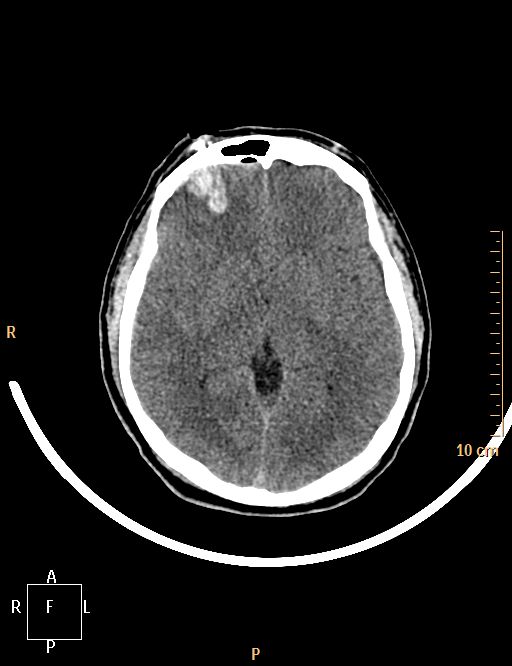

Accident de scie circulaire